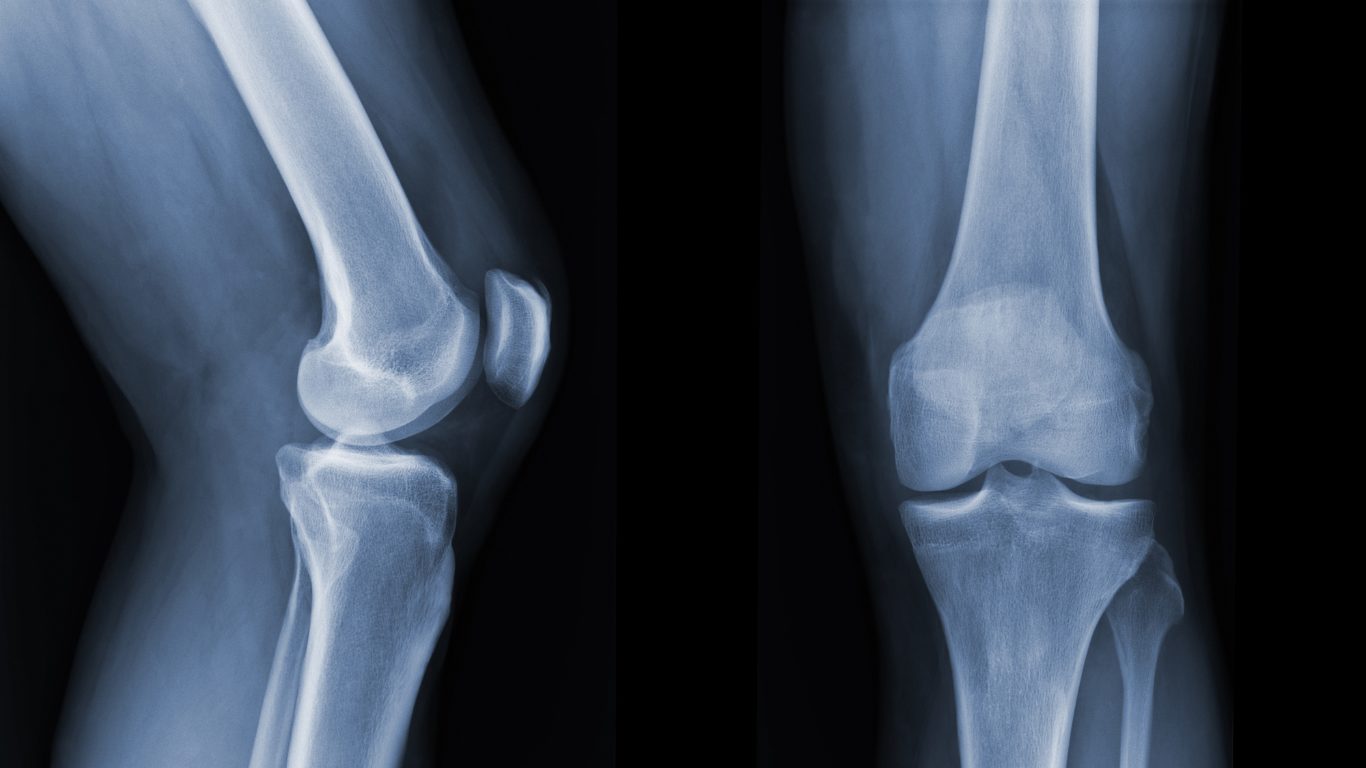

膝の痛みとして多くの方が診断を受けている病名が「変形性膝関節症」です。日本人口1億2千万人いる中で約2,500万人もの患者数がいます。そのうち、700万人が要治療患者であり、男女比が1:4で女性が男性の4倍もの数を占めています。これだけの患者数がいるにも関わらず、改善する人がいないのはなぜなのでしょうか。きっと原因が明確に分かっていないから治療法も明確にならないのだと思います。

手術以外の治療法として、ヒアルロン酸注射を紹介されるケースが多いようです。膝の動きを滑らかにして軟骨を保護することを目的に行われます。ここで膝の構造を理解してみましょう。膝の関節が正常にかみ合わないがために軟骨組織である半月板が薄れて、骨同士が干渉し、やがて変形していくのです。なので、体はそうならない為にも体内で生産した天然のヒアルロン酸(関節潤滑液)を膝に流し込むのです。しかし、膝関節がかみ合わないので天然のヒアルロン酸は溜まる一方であり、この状態を一般に「水が溜まった」といいます。注射を打つ前に溜まっている水を取り出して人口のヒアルロン酸を注入するのです。すると、何が起きるのかというと膝に溜まる液体が入れ替わるだけで関節自体は何も変わりはしないのです。これを、ひたすら繰り返すのです。このような考え方ができたならば、膝関節を正常に調整する必要があるという答えにたどり着く筈です。

しかし、先ほどの膝の役割を理解していれば膝は単体的に悪くはなりにくいもの。上半身の帳尻をとる役割がある為、骨盤に問題がある場合があります。仰向けに寝た時、骨盤が正常な人は両足のふくらはぎの裏が床についているものですが、下肢と骨盤の関係がズレていると片足が開いて、その足のふくらはぎの側面が床につく状態になります。この人が歩く場合、片足を開いてねじれて歩くだろうか。そんなことはなく、真っすぐ歩こうと無意識に体を補正するのです。下肢と骨盤の関係がズレると足の長さは違ってくるので当然、体は傾きます。そこで目線を水平にバランスをとろうとすれば、膝はねじれることによって体全体のねじれを調整しようとするのです。

変形性膝関節症はこのように、本当に膝だけの原因から起こることよりも膝から上が傾くがために、全体のバランスの中で膝がそのギャップを取り除かねばならなくなって起こる場合があります。つまり、"変形しなければならない""ねじれなくてはならない"という状況に膝が追い込まれてしまうのです。であれば、膝は二次的に起きた症状になるので原因となる膝より上の骨盤部などに注目して改善を図るべきではないでしょうか。